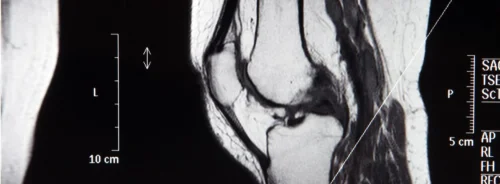

WSIs are preprocessed into tissue-containing patches and filtered to remove background using an edge-based criterion. Multiple-instance learning treats each slide as a bag of instances, enabling weak supervision when patch-level labels are unavailable. In this context, the slide label supervises learning while the model reasons over patch embeddings to infer slide-level subtype. This setting mirrors clinical practice where image patterns and narrative reports are considered together to delineate tumour characteristics and support subtype assignment.

Interpretability is addressed through attention heatmaps that highlight regions of interest at patch level on whole slides. Normalised attention scores mapped to colours help localise tumour-suggestive tissue, offering a visual explanation aligned with pathologist reviews. Illustrations compare attention patterns from baseline MIL models with the multimodal output, showing concentrated regions where tumour evidence is strongest. This transparency supports potential clinical utility by aligning model focus with tissue areas that drive classification decisions.